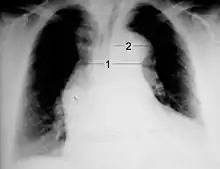

Chest X-ray

Chest radiography may demonstrate a change in the morphology of the thoracic aorta which can be seen in aortic dissection. Classically, new widening of the mediastinum on radiograph is of moderate sensitivity for detecting an ascending aortic dissection; however, this finding is of low specificity, as many other conditions can cause apparent widening of the mediastinum.

There are several other associated radiographic findings:

- The "calcium sign" describes an apparent separation of the intimal calcification from the outer aortic margin by greater than 10 mm.

- Pleural effusions, more commonly in descending aortic dissections, and typically left sided.

- Other: obliteration of the aortic knob, depression of the left mainstem bronchus, loss of the paratracheal stripe, and tracheal deviation.

Importantly, about 12 to 20% of aortic dissections are not detectable by chest radiograph; therefore, a "normal" chest radiograph does not rule out aortic dissection. If there is high clinical suspicion, a more sensitive imaging test (CT angiogram, MR angiography, or transesophageal echo) may be warranted.